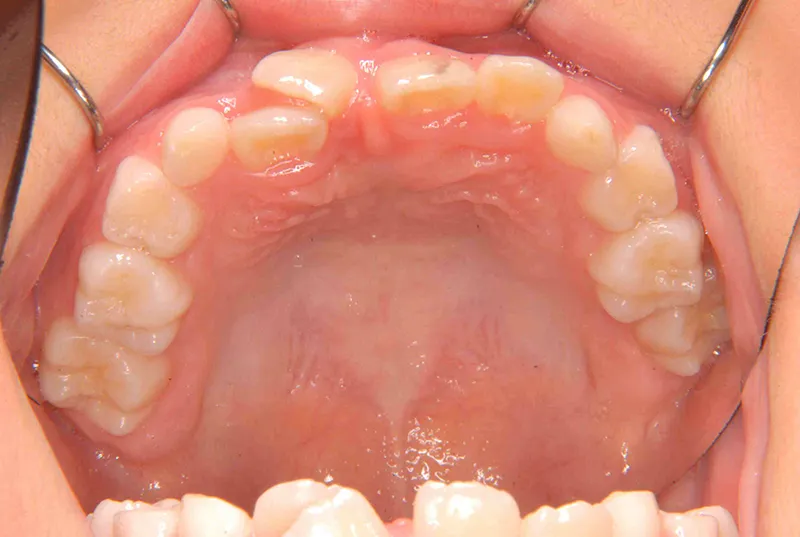

診断名 埋伏歯・反対咬合・叢生 装置名

状態 永久歯が生える隙間がない(叢生)

歯が埋まっている/歯がない(埋伏歯)

レントゲンを撮ってみると犬歯の萌出方向がずれていました。

先ずは萌出スペースを確保してから開窓術を行い、犬歯を正しい方向へ誘導しました。

初診